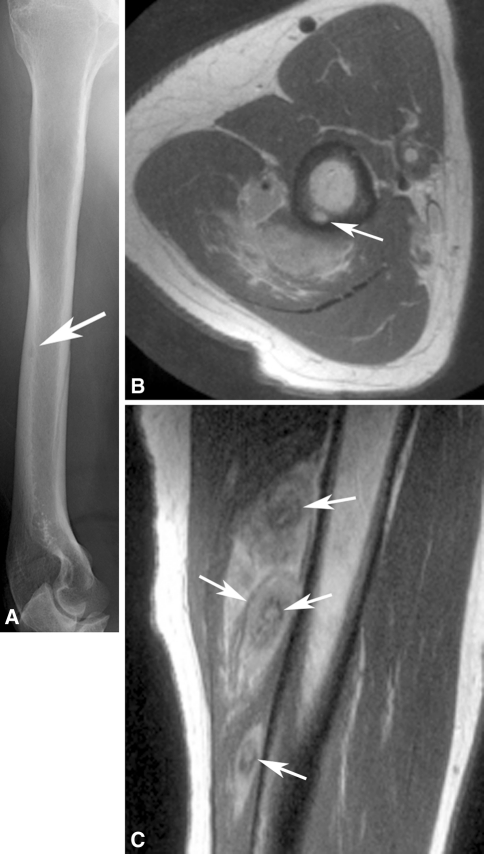

Radiologic images were available for 10 patients and were reviewed by an expert musculoskeletal tumor radiologist (DMP). The first metatarsal bone was involved in two patients (Fig. 2), and one patient each had involvement of the anterior ninth rib (Fig. 3), clavicle, T2 and T3 vertebrae, and multiple bones in a foot (Fig. 4). In the four patients with EH of soft tissue with available radiology, the lesion was located in the triceps muscle in two (Fig. 5) and one each had involvement of the flexor tendons of a hand and an index finger (Table 2).

Fig. 5A–C.

(A) The radiograph shows a tiny permeative, lytic focus in the posterior cortex of the midhumeral shaft (arrow). No calcifications are evident in nearby soft tissues. (B) An axial proton density MR image shows heterogeneous tumor deposits in the triceps muscle and an intracortical tumor deposit (arrow). (C) A sagittal proton density MR image shows multinodular tumor deposits with low-signal intensity inner rings (arrows), possibly related to hemosiderin deposition.

On radiographs the bone lesions often appeared lytic, septated, and expansile. (Fig. 2A; Table 2) The mean size of the bone lesions was 3.7 cm (range, 1.7-6 cm). One lesion showed a smooth, thick periosteal reaction. CT showed well-defined, septated, lytic lesions with cortical destruction and bony expansion (Figs. 2B, 3B). The lesions were well defined by MRI, being hypointense or isointense to muscle on T1-weighted images, and hyperintense on T2-weighted images (Fig. 4). In one patient, a small nodule of tumor extended through a region of destroyed cortex into adjacent soft tissues. Preoperative embolization images available for one patient showed an intense blush in the tumor. The mean size of the soft tissue lesions was 5.7 cm (range, 2–12 cm). Radiographs showed a small, lytic intracortical focus in the humerus of one patient (Fig. 5A) and erosion of a phalanx in another; no lesion was evident in the third. MRI showed the mass to be well defined with an unusual pattern of low-signal inner rings on proton density, T2-weighted, and gradient echo images in three of three patients (Fig. 5C). A satellite lesion was observed in one patient and a small intracortical deposit in another (Fig. 5B).